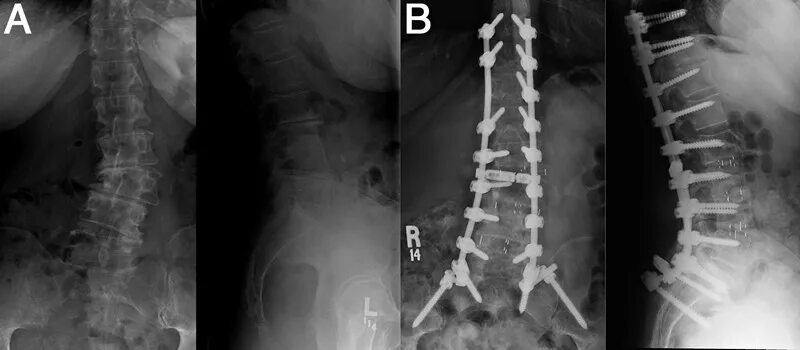

Грудопоясничный сколиоз 3 степени. 3 степени искревле искривление позвоночника. s образный кифосколиоз грудного отдела позвоночника. кифосколиоз грудного отдела позвоночника 2.Сколиоз позвоночника у детей 3 степени. искривление позвоночника у детей сколиоз 3 степени. диспластический сколиоз 2 степени. искривление позвоночника 2 степени у детей.Сколиозе степень искривления позвоночника. искривление позвоночника первой степени.Врождённый сколиоз у ребенка 3 степени. сколиоз позвоночника 3 степени. сколиоз позвоночника 3 степени инвалидность. сколиозе степень искривления позвоночника.Сколиоз позвоночника первая стадия. сколиоз позвоночника 2-3 степени. сколиоз позвоночника 1 степени градусы. 3 стадия сколиоза позвоночника.Грудопоясничный сколиоз 3 степени s образный.Степени сколиоза позвоночника по градусам у детей. 1 степень сколиоза по чаклину рентген. позвоночник при сколиозе 2 степени. сколиоз позвоночника 4 степени рентген.Сколиоз 3 степени лечениеСколиоз позвоночника 3 степени инвалидность. сколиотическая деформация позвоночника 40 градусов. инвалидность сколиоз 2 степени. s образный грудопоясничный сколиоз 2 степени инвалидность.Сколиоз спины 1 степени. сиомиоз позвоночника 1 степени. симптомы сколиоз 1 степени у детей. лечится ли сколиоз 1 степени у подростков.Искривление позвоночника у детей сколиоз 3 степени. рёберный горб сколиоз 2 степени.Сколиоз позвоночника 2 степени. инвалидность сколиоз 2 степени. сколиоз 3 степени инвалидность.Искривление позвоночника 2 степени. дугообразный сколиоз 2 степени. ii степень сколиоза характеризуется. фиксированный сколиоз 2 степени.Сколиоз 3 степени лечениеКорсет шено для шейермана мау. искривление позвоночника шейермана мау. сколиоз болезнь шейермана мау. корсет шено шейерман мао.Сколиоз поясничного отдела 3 степени. сколиоз 3 степени снимок. сколиоз 3 степени рентген после операции. диспластический сколиоз 3 степени.Корсет шено сколиолоджик. корсет функционально-корригирующий шено. корсет шено от сколиоза. корсет шено сколиоз 2 степени.Сколиоз позвоночника 4 степени. грудопоясничный сколиоз 4 степени. кифосколиоз грудного отдела 4 степени. кифосколиоз 2 грудного отдела.Сколиоз 3 степени лечениеСтепени деформации позвоночника при сколиозе. дугообразный сколиоз 1 степени. сколиоз 1 степени грудного отдела и поясничного отдела позвоночника. диагноз сколиоз 1 степени.3 степени искривления осанки. формы сколиоза позвоночника. s образный сколиоз 3 степени. сколиоз позвоночника вид сбоку.Тораколюмбальный сколиоз. ишиалгический сколиоз. сколиоз позвоночника у подростков 14 лет. раймонди сколиоз.Сколиоз 4 степени корсет шено. корсет шено s образный сколиоз. корсет эббота-шено. грудопоясничный сколиоз 3 степени рентген.Операция на сколиоз 2 степени. сколиоз операция рентген. операция на позвоночник сколиоз 2 степени. сколиоз 4 степени рентген.Сколиоз 3 степени лечениеСколиотическая деформация позвоночника. врожденный сколиоз позвоночника. тораколюмбальный сколиоз. правосторонний сколиоз th6-th7.Сколиоз позвоночника 1 степени. левосторонний сколиоз 2й степени. правосторонний сколиоз 1 ст. правосторонний и левосторонний сколиоз.Сколиоз 1 степени сбоку. сколиоз 10 градусов рентген.Корсет шено при сколиозе 4 степени. корсет шено сколиоз 2-3 степени. корсет шено s образный сколиоз.Сколиотическая деформация позвоночника. сколиотическая деформации позвоночника 1-2 степени. кифосколиоз грудного отдела позвоночника.Искривление позвоночника сколиоз. идиопатический сколиоз грудного отдела позвоночника. сколиотическая деформация позвоночника. сколиоз поясничного отдела 3 степени.S образное искривление позвоночника 3 степени. сколиоз поясничного отдела позвоночника по степеням. s образный сколиоз 1 степени по чаклину. сколиоз 2 степени угол искривления.Сколиотическая дуга. дугообразное сколиотическое искривление. сколиоз с 3 дугами искривления. сколиозы 4 степени деформации.Сколиоз 1 степени симптомы. искривление позвоночника 1 степени. этапы сколиоза.Грудопоясничный сколиоз 3 степени s образный. корсет шено s образный сколиоз. сколиоз позвоночника 2 степени.Корсет шено шейерман мау. корсет шено сколиоз 2-3 степени. корсет шено для шейермана мау. сколиоз 3 степени корсет шено.Корсет шено шейерман мао. сколиоз корсет шено. корсет шено кифоз. сколиоз 3 степени корсет шено.Идиопатический правосторонний грудопоясничный сколиоз 2 степени. идиопатический правосторонний грудопоясничный сколиоз 1 степени. идиопатический сколиоз грудного отдела позвоночника. идиопатический грудопоясничный сколиоз 3 степени.Сколиоз корсет шено. сколиоз в подростковом возрасте.Корсет шено кифоз. корсет шено и гимнастика шрот. корсет шено s образный сколиоз. корсет шено при кифозе.Сколиоз 3 степени корсет шено. корсет шено сколиоз 2 степени. корсет шено s образный сколиоз. s образный сколиоз 2 степени грудного отдела.Презентация на тему сколиоз. сообщение на тему сколиоз. сообщение о искривлении позвоночника. сколиоз доклад по биологии.Методики лечения сколиоза. рекомендации врача при сколиозе. сколиоз 1 степени лечится.Сколиоз позвоночника 2-3 степени. сколиоз 2 степени по чаклину. сколиоз позвоночника 1 степени. левосторонний сколиоз 3-4 степени.Градусы искривления позвоночника. 25 градусов искривление позвоночника. сколиоз позвоночника 25 градусов. искривление позвоночника 11 градусов.Сколиоз кифоз грудного отдела. позвоночник сколиоз грудного отдела позвоночника. сколиоз кифоз 3 степени.Искривление позвоночника 3 степени. искривление позвоночника 2 степени.Нейрофиброматоз сколиоз. миопатический сколиоз. клиника сколиоза позвоночника.Сколиоз корсет шено. сколиоз 3 степени корсет шено. корсет шено сколиоз 2-3 степени. сколиоз 4 степени корсет шено.Операция харрингтона сколиоз. метод харрингтона сколиоз рентген. дистрактор харрингтона. сколиоз 4 степени рентген.Кифосколиоз грудного отдела позвоночника 1. правосторонний и левосторонний сколиоз. идиопатический сколиоз грудного отдела позвоночника. кифосколиоз пояснично крестцового отдела.Идиопатический грудопоясничный сколиоз. идиопатический грудопоясничный сколиоз 1 степени. юношеский сколиоз 2-3 степени.Сколиоз 3 степени корсет шено. шено при сколиозе 4 степени. корсет шено сколиоз 2-3 степени. сколиоз 4 степени корсет шено.Сколиоз боковое искривление позвоночника. идиопатический сколиоз 3 степени. диспластический кифосколиоз. идиопатический s-образный сколиоз 4 степени..Сколиоз 3 степени операция. сколиоз 4 степени рентген операция. операция на позвоночник сколиоз 3 степени. операция харрингтона сколиоз.Паралитический сколиоз. сколиоз кифоз 3 степени. миопатический сколиоз. кифоз позвоночника 4 степени.Сколиоз 3 степени лечениеСколиоз позвоночника горб. рёберный горб сколиоз 2 степени. рёберный горб сколиоз 3-4 степени. сколиоз позвоночника схема.Сколиоз грудного отдела позвоночника. боковое искривление позвоночника. сколиоз позвоночника 2 степени.Кифосколиоз грудного отдела позвоночника. сколиотическая деформация позвоночника. сколиоз позвоночника сколиоз.Корсет шено кифоз. корсет шено для позвоночника кифоз. корсет шено сколиоз 2 степени. корсеты шато при сколеозе.Статистический сколиоз. упражнения для s образного сколиоза 3 степени. стабильность позвоночника.Сколиоз позвоночника правосторонний 2 степени. s образный сколиоз грудного и поясничного отдела 2 степени. левосторонний грудопоясничный сколиоз. левосторонний s образный сколиозе 2 степени.Сколиоз 1-2 степени. сколиоз 2 степени презентация. паралитический сколиоз.Сколиоз 2 степени искривление 17 градусов. фиксированный сколиоз 2 степени при угле искривления 17 градусов. сколиоз отклонение 1 степень. угол искривления при сколиозе 2 степени.Сколиоз 3 степени лечениеСколиоз 3 степени лечениеСколиоз позвоночника влево. отклонение оси позвоночника вправо в грудном отделе. сколиоз отклонение 1 степень. сколиоз позвоночника первая стадия.Дистрактор харрингтона. сколиоз 4 степени рентген. операция на позвоночнике сколиоз 4 степени. сколиоз позвоночника 4 степени рентген.Анталгический сколиоз. левосторонний грудопоясничный сколиоз. сколиоз грудного отдела позвоночника 2 степени. s образный сколиоз грудного отдела позвоночника.Корсет эббота-шено. корсет шино шино. дикуль корсет шено. сколиоз 3 степени корсет шено.Сколиоз описание. z образный сколиоз. сколиотическая болезнь позвоночника.Грудопоясничный сколиоз 3 степени s образный. сколиоз позвоночника у взрослых 3 степени. s образный грудопоясничный сколиоз 2 степени. s образный сколиоз 2 степени поясничного отдела.Идиопатический s образный сколиоз. с образный сколиоз 4 степени. s образное искривление позвоночника. сколиоз 2 степени s образный идиопатический.